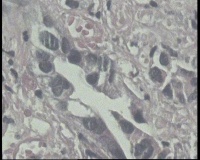

请教,胃溃疡,癌变吗?

胃窦溃疡性病变

胃窦变形,粘膜变薄,粘膜下血管网透见,前壁见不规则溃疡1.6x1.4lm ,周围粘膜呈不规则隆起

活检组织4块。请老师看看高级别癌变吗?倒数第4图纤维间质内腺体,是浸润吗?

可以报癌了。

腺癌。

腺癌,黏膜肌层浸润。